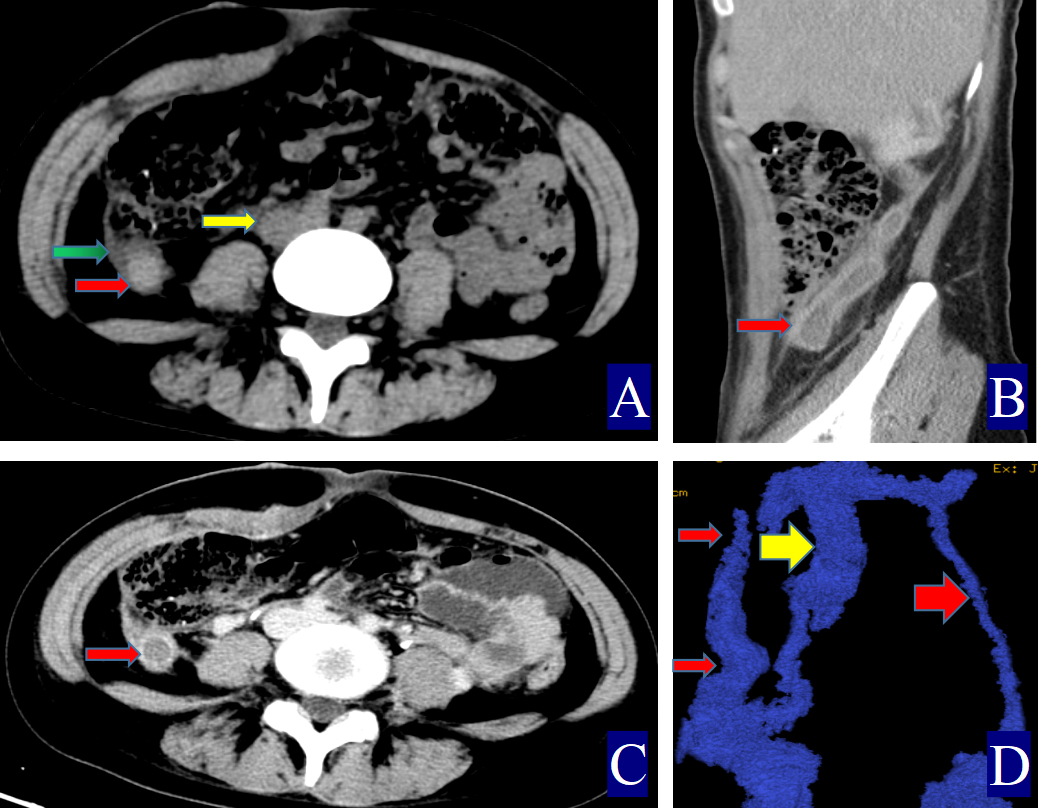

Fig. 1. A 24-year-old woman with right ovarian vein thrombophlebitis. The red arrow indicates the ovarian vein, the yellow arrow indicates the inferior vena cava, and the green arrow indicates the periovarian vein exudate. (A) Non-contrast axial CT image. The right OV is approximately 1.4 cm wide (CT value = 52.00 HU, red arrow). The inferior vena cava shows a CT value of 32.40 HU (yellow arrow), with visible surrounding exudation (green arrow). (B) Contrast-enhanced sagittal CT image. A filling defect is observed in the right ovarian vein, consistent with POVT, and the vessel wall appears uniformly thickened (red arrow). (C) Contrast-enhanced axial CT image. The right ovarian vein shows a clear filling defect, and the vessel wall is uniformly thickened (red arrow). (D) Three-dimensional vein reconstruction. The inferior vena cava is marked (yellow arrow), with the right OV shown as a thin red arrow and the left OV as a thick red arrow.

The primary CT findings of POVT included filling defects within the ovarian vein lumen along with thickening of the vessel wall (Figs. 1,2,3). Secondary signs involved pelvic effusion in 13 cases and periovarian venous exudation with increased fat density in 19 cases (Figs. 1A,C,3A,C). One patient, who developed extensive thrombosis extending to both lower extremity veins, the inferior vena cava, and pulmonary arteries, died from postpartum hemorrhagic shock. The remaining 23 patients fully recovered.

Compared with the non-POVT group, the POVT group showed significantly greater ovarian vein width on the thrombus side, higher CT attenuation of the thrombus-side ovarian vein, as well as increased CT attenuation difference and ratios (p = 0.001, Figs. 1,2,3). Using 0.90 cm as the cut-off value for ovarian vein width, the sensitivity reached approximately 91.70%, with a specificity of 95.20% (Figs. 1A,2A,3A,C,D). With 46.00 HU as the threshold for ovarian vein CT value on the thrombus side, both sensitivity and specificity were 100% (Figs. 1A,2A,3A). For a CT attenuation difference cut-off of 12.50 HU, the sensitivity was 95.30%, and specificity remained 100%. Similarly, a ratio cut-off of 1.1 yielded a sensitivity of 95.30% and specificity of 100% (Figs. 1A,2A,3A).

Direct signs observed on CT included variable widening of the ovarian vein, increased intraluminal density, and filling defects, often accompanied by vessel wall thickening, which is in line with prior reports [16, 17, 18, 19, 20, 21] (Figs. 1,2,3). A notable finding in our study was the identification of previously undescribed indirect signs: increased fat density around the ovarian vein in the pelvis and the presence of small-volume pelvic effusion (Figs. 1A,3A–D). These signs may reflect the local inflammatory reaction associated with thrombophlebitis.

Semi-quantitative parameters from non-contrast CT scans revealed clear differences between the POVT and non-POVT groups. The thrombus-side ovarian vein width, CT attenuation of the thrombotic ovarian vein, the difference between ovarian and inferior vena cava CT values, and their ratio were all significantly higher in the POVT group (p = 0.001, Figs. 1,2,3). These parameters may serve as reliable diagnostic references. For instance, using 0.90 cm as the cut-off for ovarian vein width yielded a sensitivity of approximately 91.70% and a specificity of 95.20%. This supports earlier findings [5] that vein enlargement is a key feature of POVT (Figs. 1,2,3). A CT attenuation cut-off of 46.00 HU for the thrombotic ovarian vein achieved 100% sensitivity and 100% specificity (Figs. 1,2,3). Similarly, a CT attenuation difference threshold of 12.50 HU and a ratio cut-off of 1.1 also demonstrated strong diagnostic performance (Figs. 1,2,3). However, in one patient with extensive thrombosis of the inferior vena cava, the ovarian vein had a lower CT value than the cava, resulting in a negative difference (–12.50 HU) and a ratio of 0.83, reflecting variability in advanced or complex cases. Currently available non-invasive diagnostic tools for POVT include Doppler ultrasound (sensitivity 52%), magnetic resonance imaging (MRI) (92%), and contrast-enhanced multidetector CT (100%) [5]. The present study indicates that non-contrast CT semi-quantitative parameters can closely match the diagnostic accuracy of enhanced CT, while offering greater simplicity, lower cost, and avoiding the risks associated with contrast agent use.